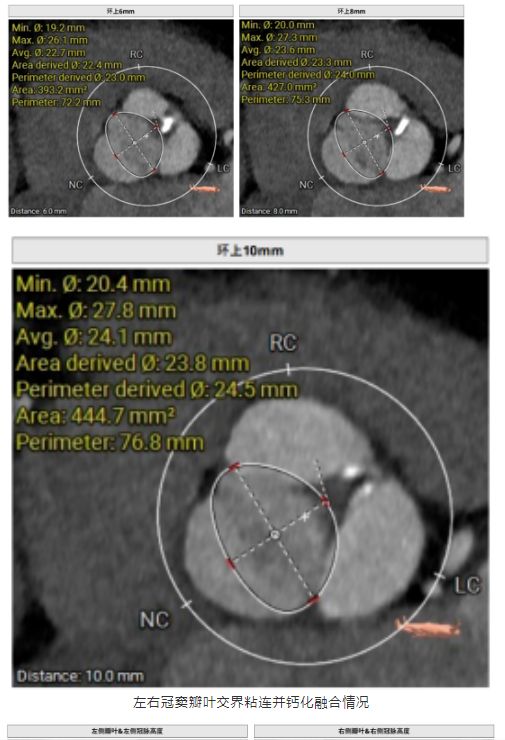

術前超聲和CTA評估提示,患者Type1型二葉主動脈瓣,瓣葉稍增厚,左右冠竇瓣葉交界粘連并鈣化融合,存在三個瓣竇,分布較均勻。主動脈瓣環(huán)直徑26.5mm,左心室流出道直徑27.9mm,STJ直徑31.9mm, 升主動脈擴張,直徑41.7mm;左、右冠脈高度與瓣葉長度適中;左室主動脈夾角為125°,心尖-主動脈夾角偏大。

術前,手術團隊針對該特殊的I型二葉瓣瓣膜結構,制定了精確的操作策略。患者左右冠竇瓣葉融合合并鈣化,可能使瓣架受擠壓,導致術中定位與釋放難度顯著高于常見的三葉瓣病例。同時,其左心室主動脈夾角為125°,使其軸向的調整難度明顯加大。在術前充分評估難度及風險后,團隊根據該二葉瓣的解剖變異,制定了個性化的手術方案,術中更加精細操作,最終手術團隊順利完成瓣膜植入。